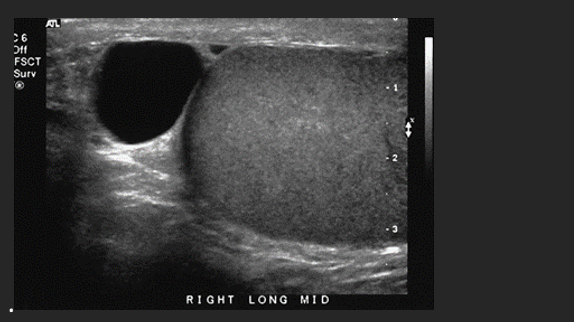

A 45 year old patient presents with acute scrotal pain after a mountain biking trip. On the basis of this clinical history, the sonographic findings are most suspicious for what abnormality?

An echogenic mass is identified superior to the testis and outlined by calibers. This most likely represents what structure?

C. Epidymitis

C. Head of the Epidymis